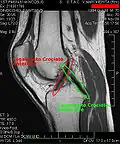

MRI

Both anterior cruciate ligament (ACL) and posterior cruciate ligaments (PCL) are hypointense on both T1 and T2 weighted images of MRI. However, some high signal striations are often seen at the distal part of the ACL, making ACL higher intensity than PCL on MRI scans.[20]